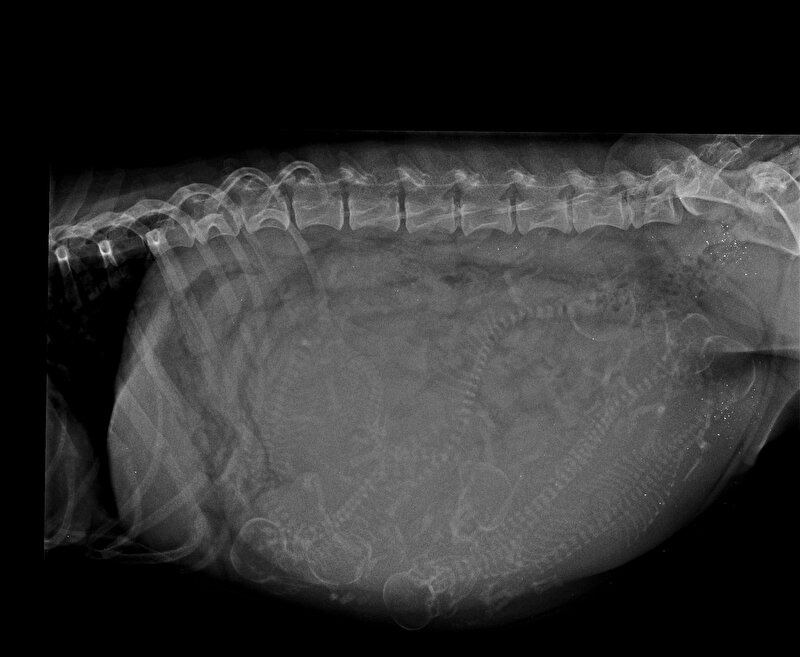

Op 6 februari is Sebbie uiteindelijk gedekt. En nog geen vijf weken later kunnen we eigenlijk al wel met zekerheid zeggen dat ze drachtig is! Ze begint nu al mooi te veranderen en is zelfs al dikker dan ze de vorige keer met 7 weken was. Dat belooft dus wat…